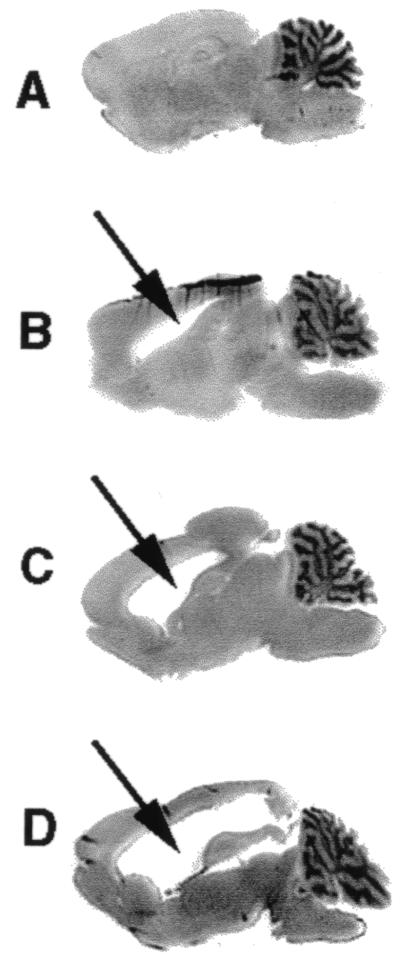

An example of the range in hydrocephalus severity is shown in Fig. 1, and the resultant RNVT scores are shown in Fig. 2A. Based on the RNVT scores, distinctions could be made in the relative neurovirulence (i) between vaccine and wild-type strains, (ii) among wild-type strains, and (iii) among vaccine strains. Differences in RNVT scores between vaccine and wild-type strains were significant (P < 0.001 for all scores compared) and paralleled the known clinical histories of these strains. While there have been no confirmed cases of strain JL- or JL-RIT-induced CNS infection, infection of the CNS occurs in up to 1% of Ur-AM9 vaccinees and in approximately 50% of cases of infection by wild-type mumps viruses (3, 4, 14). Among the wild-type strains, RNVT scores of strains 88-1961 and Kilham were greater than that of Lo1 (P ≤ 0.001 for all scores compared), consistent with the known neurovirulence of the three strains. Of note, the RNVT scores of strains 88-1961 and Kilham were equivalent, suggesting that while species adaptation may account for the high scores of the Kilham strain, neurovirulent human isolates can exhibit high RNVT scores in the absence of adaptation to rodents. Differences between Ur-AM9 and the JL-based vaccine strains were also significant (P < 0.02 for all scores compared) and consistent with their clinical histories as cited above. Differences in RNVT scores between JL and JL-RIT and between Ur-AM9 and Ur-1004 were not statistically significant.

FIG. 1.

Representative sagittal brain sections from rats inoculated with mumps virus. Arrows indicate the lateral ventricle. (A) No hydrocephalus; (B) mildly enlarged ventricle occupying 6% of the total brain cross-sectional area; (C) moderately enlarged ventricle occupying 12% of the total brain cross-sectional area; and (D) severely enlarged ventricle occupying 26% of the total brain cross-sectional area. The sections were stained with hematoxylin and eosin. Magnification, ×1.5.